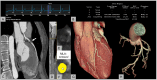

Cardiac computed tomography (CT) was introduced in the late 1990's. Since then, an increasing body of evidence on its clinical applications has rapidly emerged. From an initial emphasis on its technical efficiency and diagnostic accuracy, research around cardiac CT has now evolved towards outcomes-based studies that provide information on prognosis, safety, and cost. Thanks to the strong and compelling data generated by large, randomized control trials, the scientific societies have endorsed cardiac CT as pivotal diagnostic test for the management of appropriately selected patients with acute and chronic coronary syndrome. This consensus document endorsed by the European Association of Cardiovascular Imaging is divided into two parts and aims to provide a summary of the current evidence and to give updated indications on the appropriate use of cardiac CT in different clinical scenarios. This first part focuses on the most established applications of cardiac CT from primary prevention in asymptomatic patients, to the evaluation of patients with chronic coronary syndrome, acute chest pain, and previous coronary revascularization.